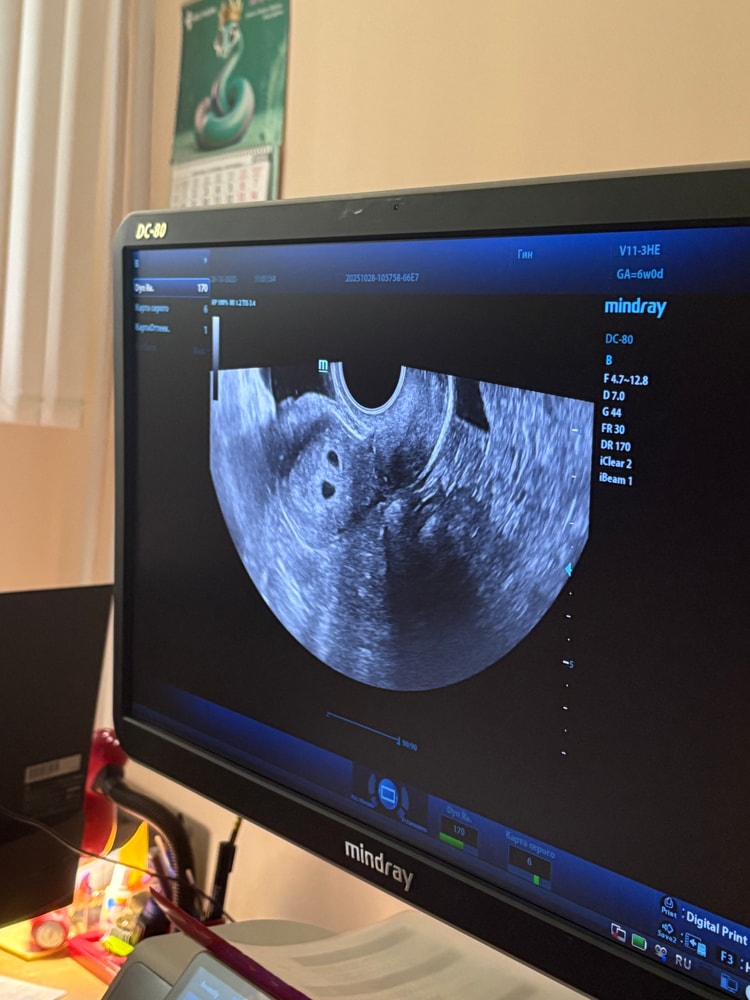

Двойня же🥰 поздравляю вас от всей души 🌺

Чудесно! Это дихориальная беременность (двойняшки). Пусть беременность будет легкой и малыши родятся в срок 🥰✨